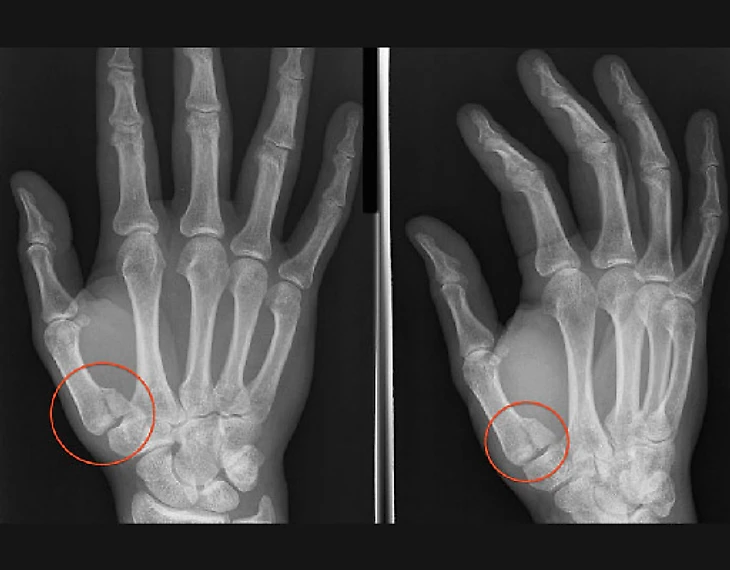

Удар по кончику пальца. Такой механизм характерен для спиральных и вколоченных переломов, например таких.

Возникают они при прямом попадании мяча в кончик пальца, неудачном приземлении или контакте с соперником. Особенность этого вида переломов в том, что сила направлена внутрь кисти и может также придавать вращение пальцу, из-за чего линия перелома проходит косо вдоль пальца, и такой перелом можно вылечить лишь при помощи хирургической фиксации.